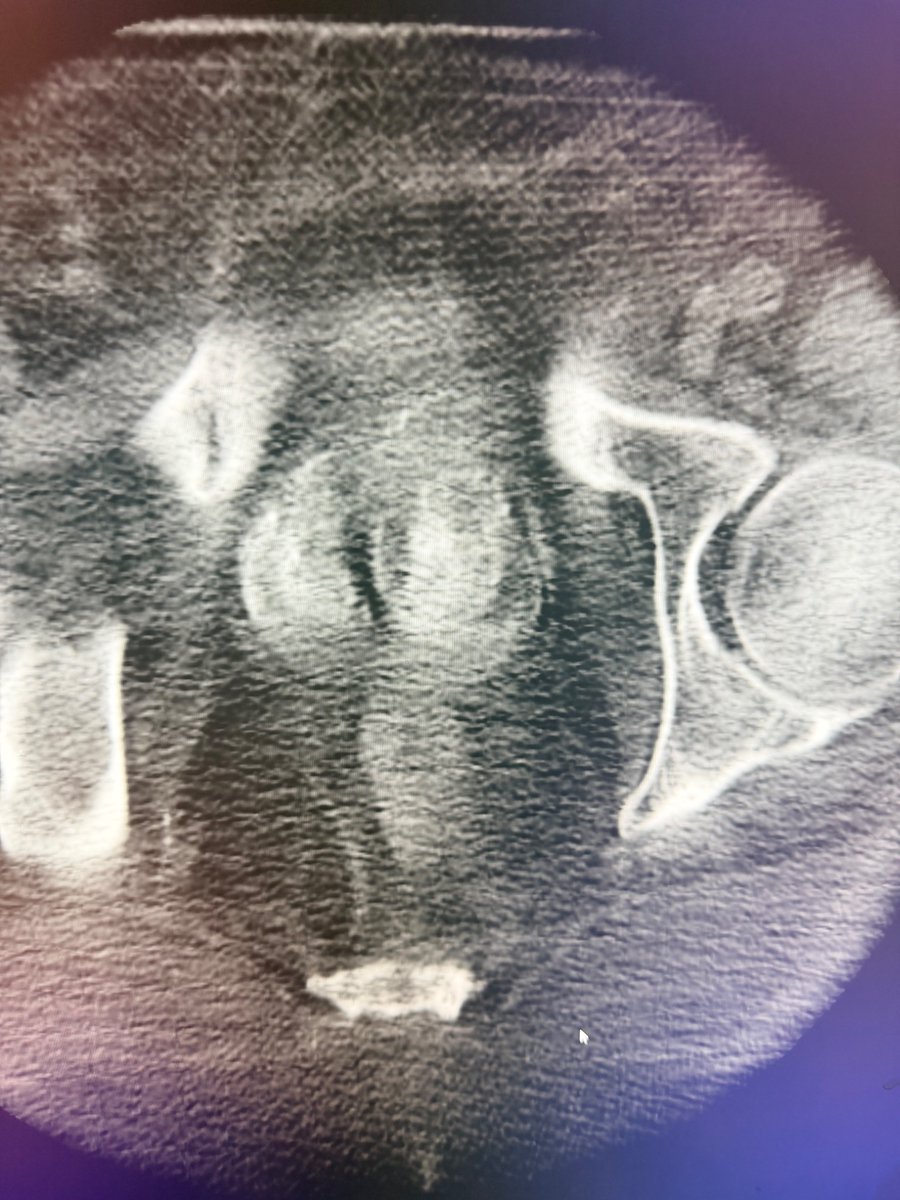

Dr. Kim published a case report in the Journal of Vascular & Interventional Radiology detailing a unique prostate artery embolization procedure. The report highlights the clinical approach & outcomes of this minimally invasive treatment for BPH. @DrGluRu jvir.org/article/S1051-…